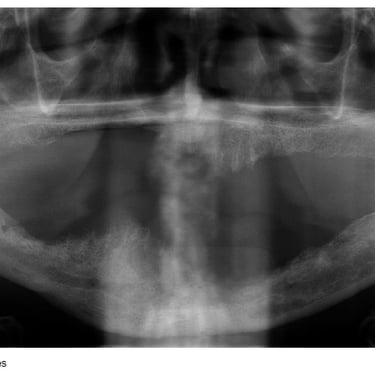

Atrofia ósea alveolar

La atrofia ósea alveolar es la pérdida de hueso en la mandíbula o el maxilar debido a la ausencia prolongada de dientes.

Los pacientes pueden notar que sus encías están hundidas y que las dentaduras no encajan bien.

El tratamiento puede incluir injertos óseos para preparar el sitio para la colocación de implantes.

Falta de hueso para implantes

La falta de hueso suficiente para la colocación de implantes puede ser una barrera para el tratamiento.

Los pacientes pueden ser informados de que no tienen suficiente hueso en la mandíbula o el maxilar para soportar un implante.

El tratamiento incluye técnicas de regeneración ósea, como injertos óseos, para aumentar el volumen óseo.